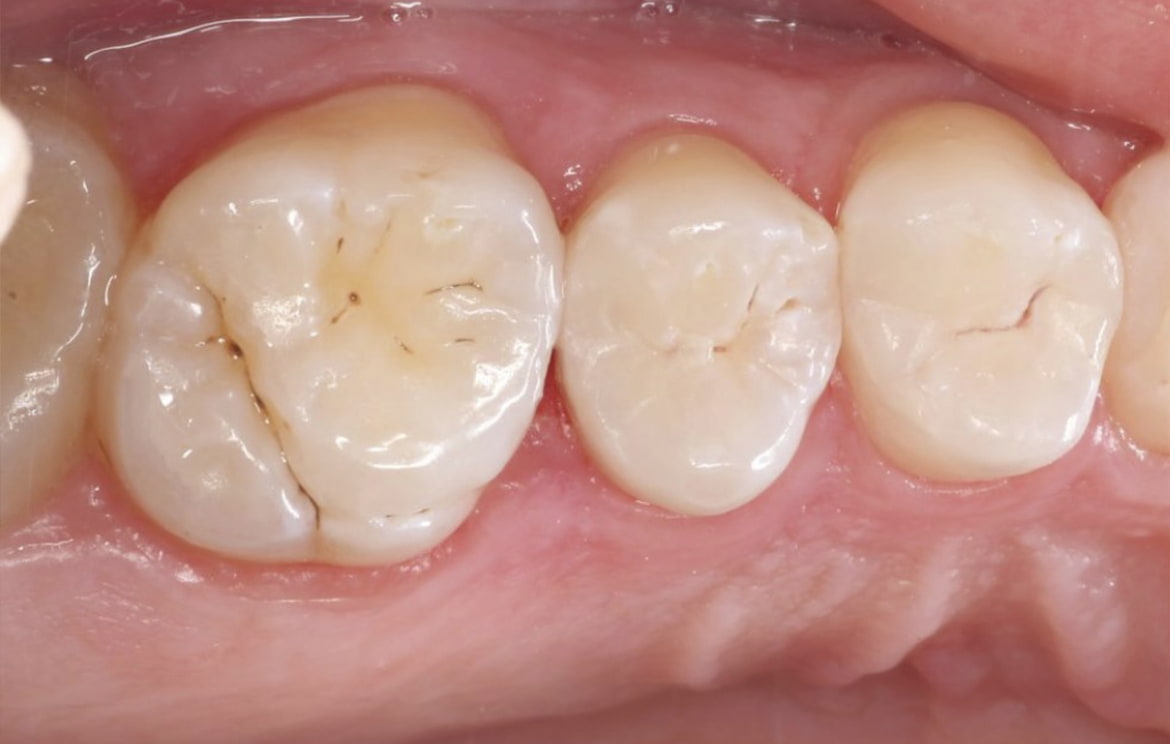

Наши работы